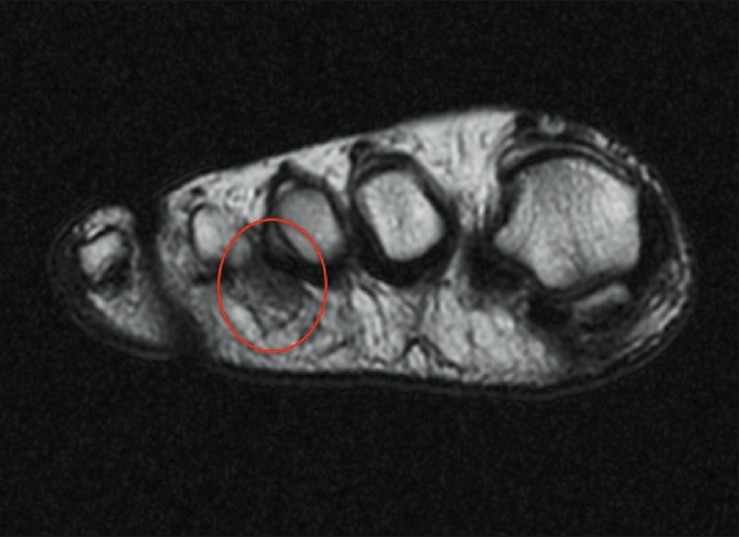

세번째 지간공간에서 발견할 수 있는 지간신경종(Morton neuromas). T1 강조 영상

더블클릭을 하시면 이미지를 수정할 수 있습니다

세번째 지간공간에서 발견할 수 있는 지간신경종(Morton neuromas). T2 강조 영상